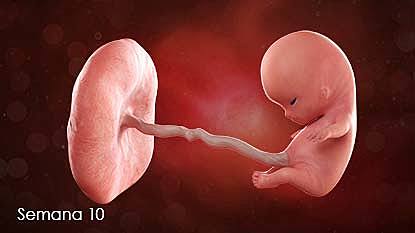

• Semana 10

10

Semana 10

-Se deja de usar la palabra embrión para denominarlo feto.

-Las medidas del feto rondan los 4 centímetros y su peso los 5 gramos.

-Se desarrollan parpados, orejas y cara.